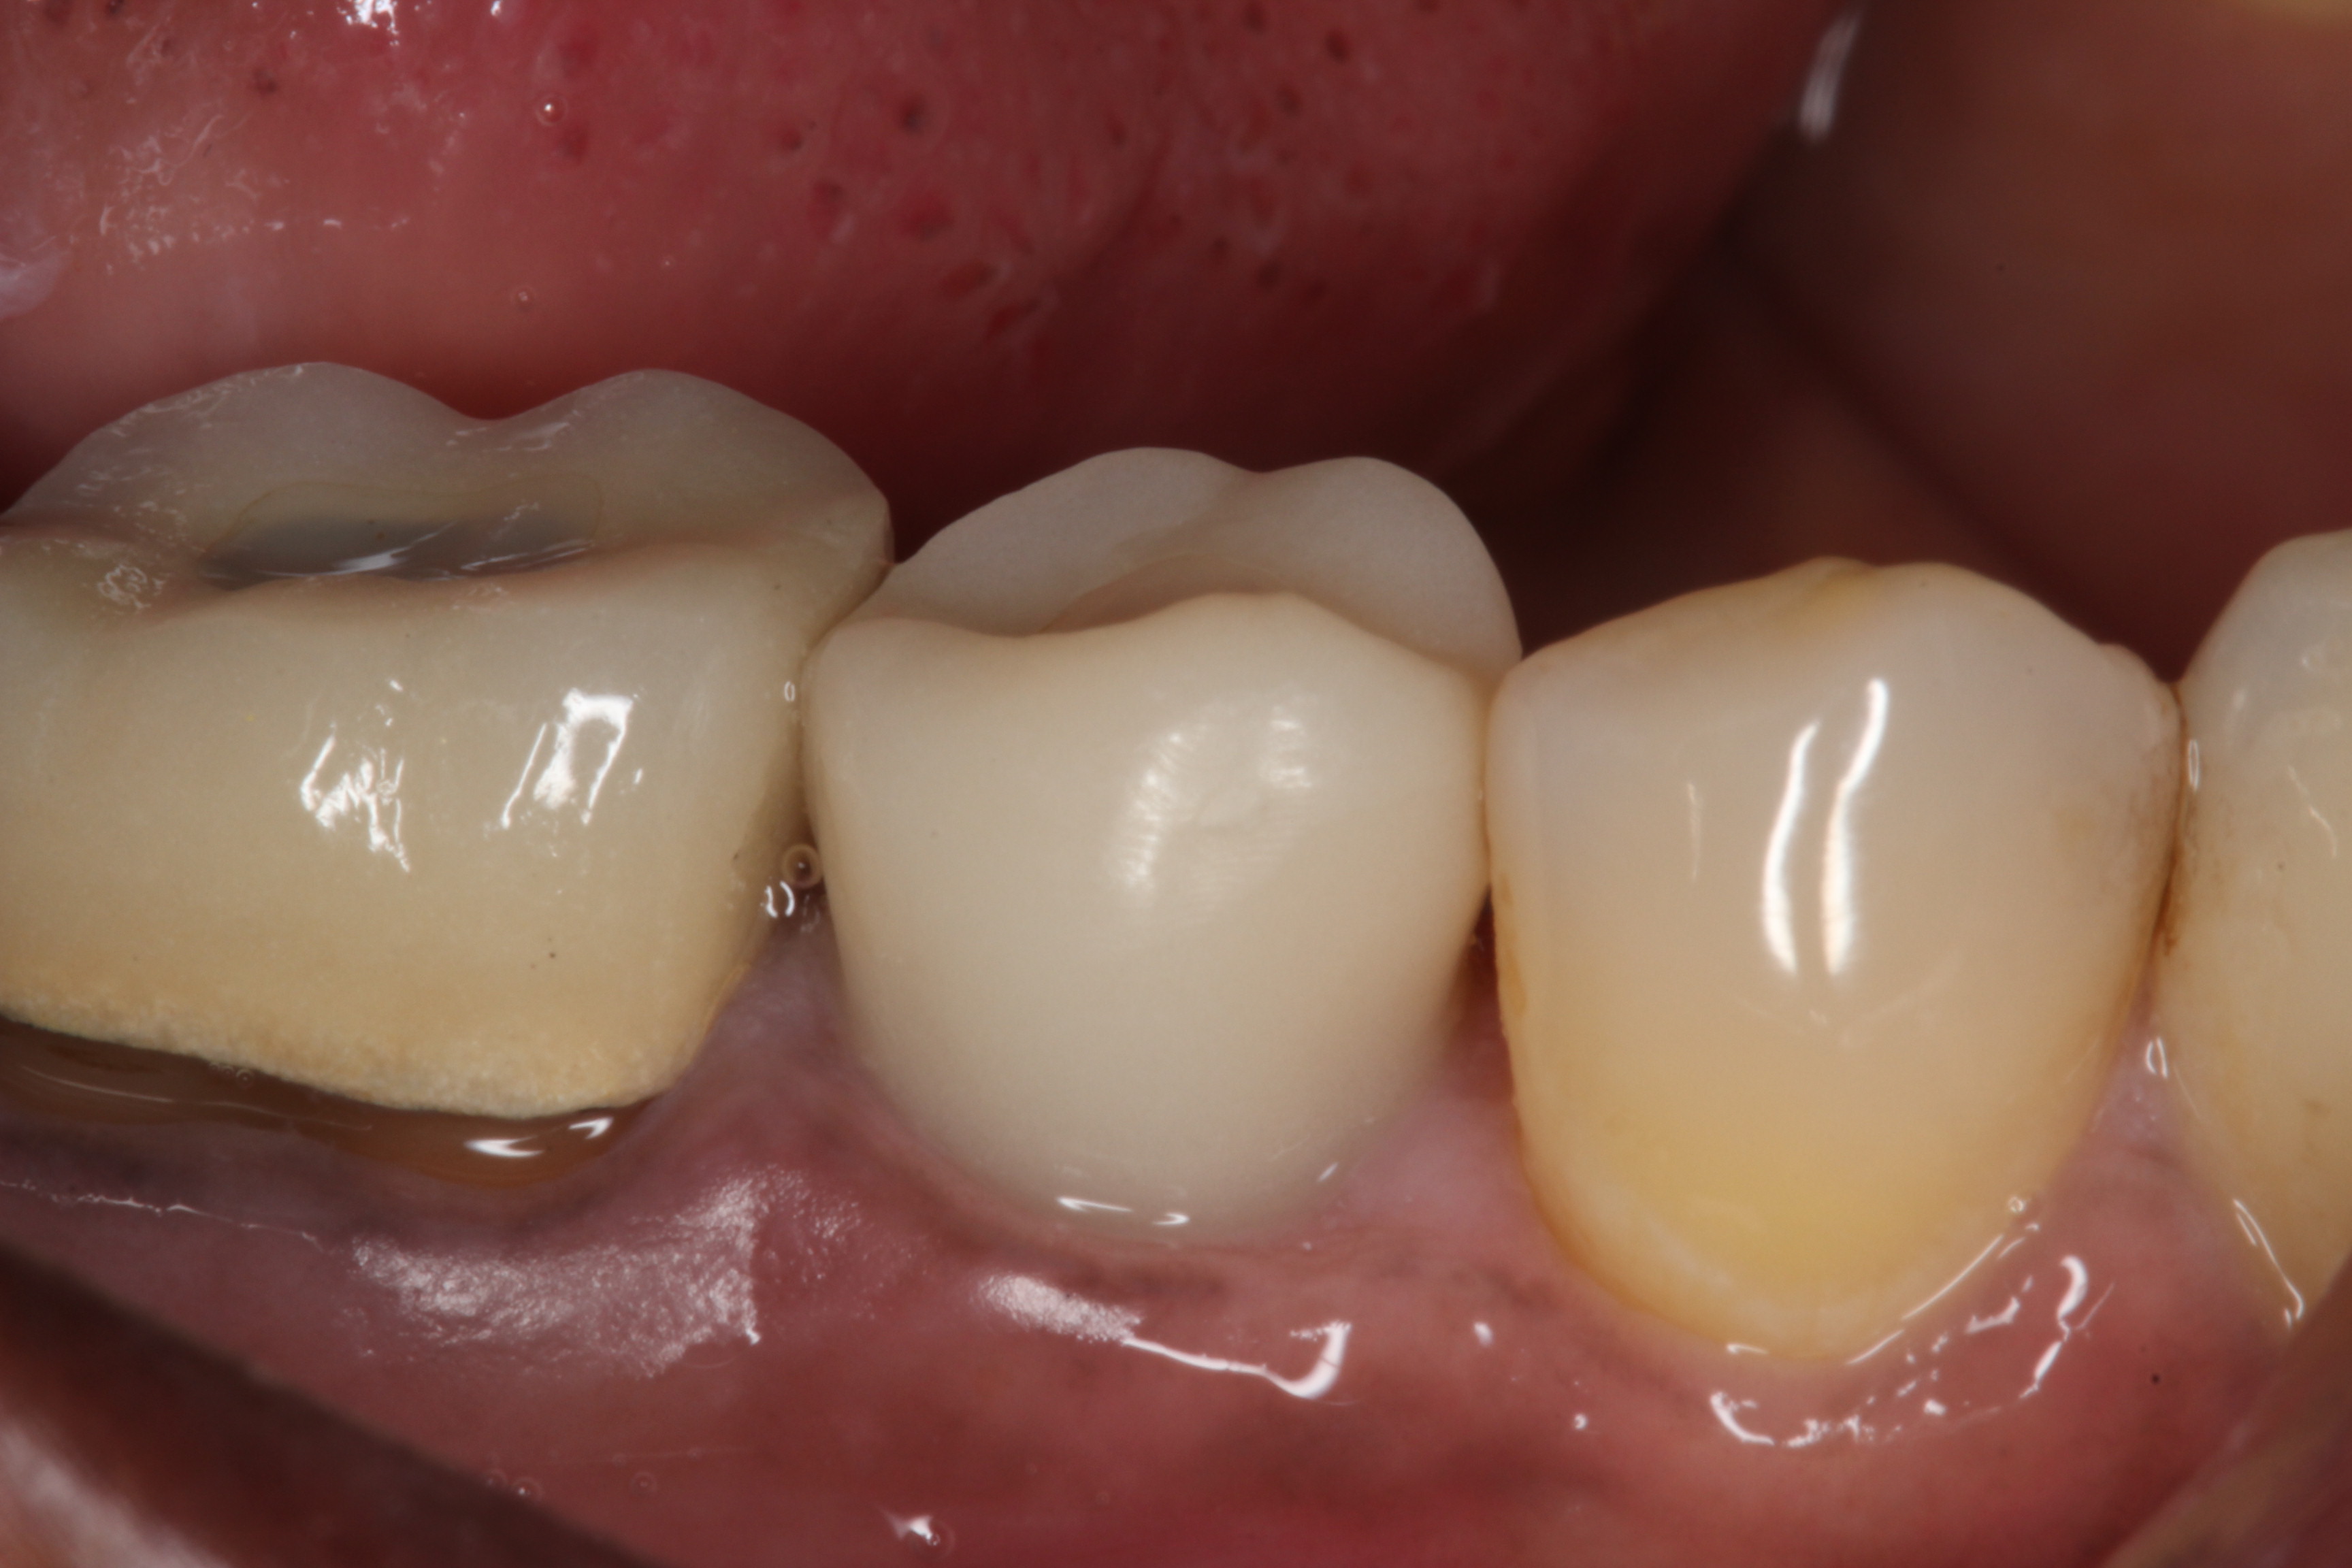

Results: This alternative CAD/CAM fabrication method was successfully used in a number of clinical cases with excellent results (see images). Although the milled portion of the crown accommodated the TiBase, it did not fit as precisely as that achieved with the normal procedure using an A16 block and scanning utilizing a scan body. However, after cementation good retention was achieved between the TiBase and the milled provisional restoration.

Conclusions: Although, it is suggested that a screw-retained provisional implant resin restoration cannot be fabricated using the Compact Milling Machine, the present authors were able to develop a successful work-around protocol for fabricating a screw-retained implant provisional crown using a 40 mm Telio® CAD Bridge Block, instead of the normally utilized A16 block. For those clinicians who have not upgraded and still use a Compact Milling Unit, the present authors offer an innovative CAD/CAM process to fabricate a provisional resin implant crown.